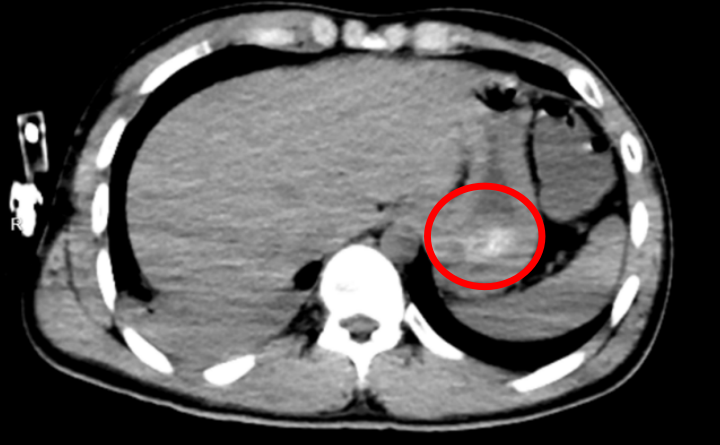

全腹CT结果验证这一判断:他的胃底可见大量团块状高密度影,正是那团凝结的药物;同时,胸部CT也提示,双肺出现渗出性病变,右肺下叶尤为严重,已经出现了吸入性肺炎。

也就是说,导致林浩昏迷不醒的——正是胃里还在持续释放毒性的药团,再叠加吸入性肺炎。

如果不能尽快清除药团,多器官功能衰竭、死亡将接踵而至。